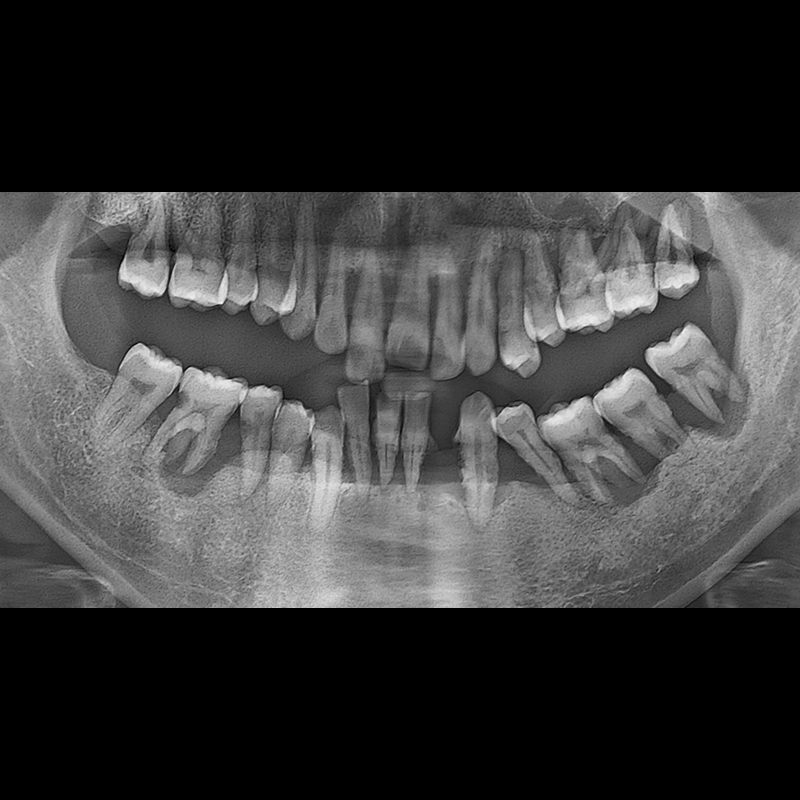

BEFORE AFTER

임플란트 전후사진 2025.05.30

결손된 치아 부분과 살리기 힘든 치아 위치에 임플란트를 식립하였습니다.